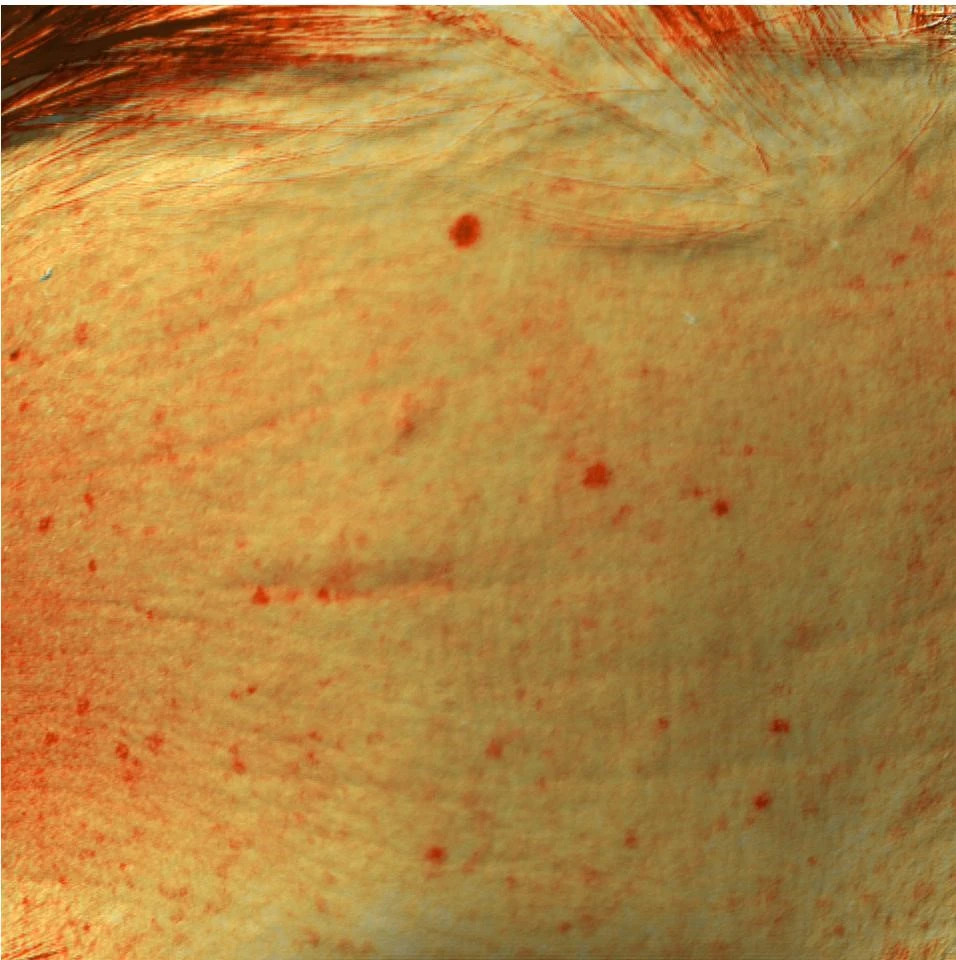

Также для фотодокументации клинических результатов был применен аппарат трехмерной визуализации поверхности кожи Antera 3D. Он предназначен для оценки состояния сосудистого компонента, интенсивности гиперпигментации, глубины залегания морщин различного калибра, ширины и количества пор, а также рельефа тканей. В данном исследовании использовалось документирование в режиме «меланин».

Комбинированный протокол IPL и Bellarti Hydrate

После терапии